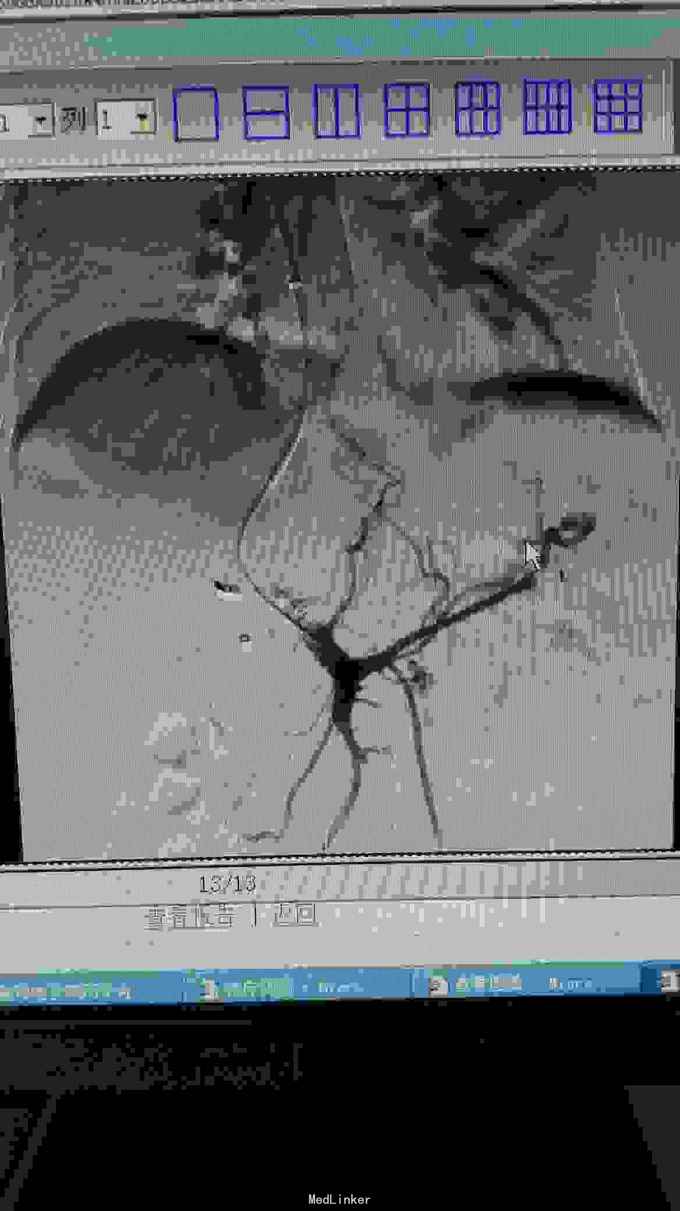

TIPS术后限流性支架植入

72女性,乙肝肝硬化门静脉高压合并肝动脉门静脉瘘,外院行肝动静脉瘘栓塞,术后出现消化道出血、顽固性腹水、门静脉血栓,转我院后给予性TIPS,术后12小时转氨酶快速升高,考虑分流过度、肝衰,24小时内行限流术,术后48小时转氨酶明显降低,术后7天安全出院。